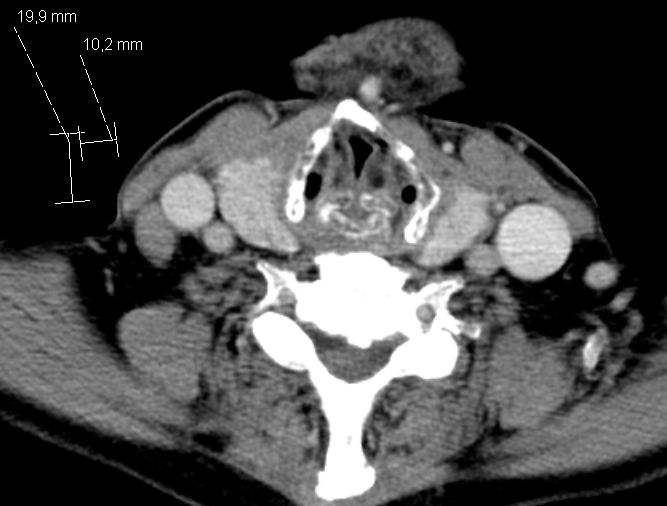

Paraaortale LK |

Befall der Nl. paraaortales links![]() | |||